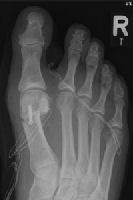

Lapidus-Arthrodese:

Die Versteifung im TMT-Gelenk (der Gelenkverbindung zwischen der Fußwurzel und dem 1. Mittelfußstrahl) ist fortgeschrittenen Fällen vorbehalten, bei denen neben einer Hallux valgus Fehlstellung der Großzehe auch eine erhebliche Lockerung des Bandapparates im inneren Fußwurzelbereich vorliegt. Diese Operation wird bei ausgeprägten Hallux valgus Fehstellungen angewendet. Das lockere innere Fußgewölbe, welches zur Vorfußdeformität geführt hat, wird stabilisiert. Ziel der Operation ist neben der korrekten Ausrichtung der Großzehe, die Belastungsfähigkeit des inneren Fußgewölbes zu rekonstruieren. Dies erfolgt mittels einer winkelstabilen Titanplatte. Eine postoperative Teilentlastung für 4-6 Wochen mit Unterarmgehstützen bis zur knöchernen Ausheilung ist erforderlich.